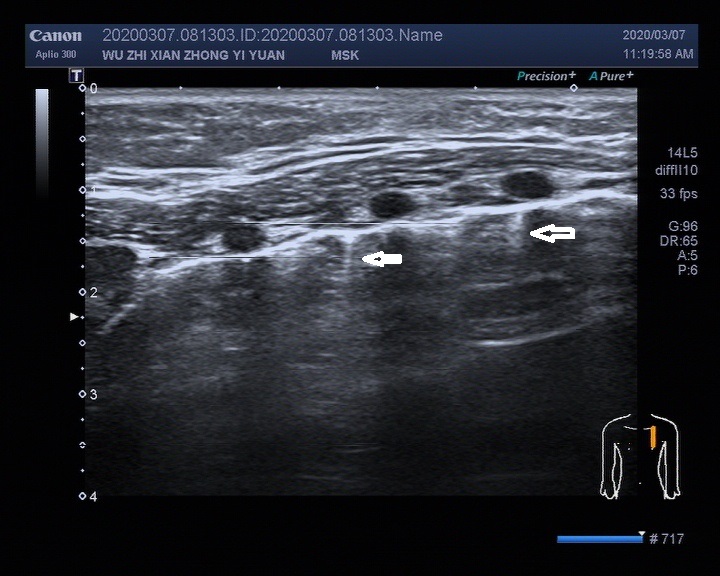

▎5个月婴儿肺脏超声检查超声图像

image009

白色箭头所示:右锁骨中线2-4肋间可见散在片状实性低回声结节,较大的约4.6x2.5mm,局部A线显示不清,2-5肋间可探及散在B线。